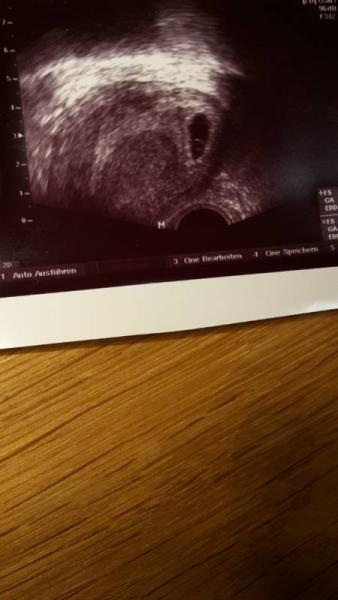

Die Fruchthöhle und den Dottersack hat man gesehen. Alles regelrecht entwickelt. Bin erleichtert

Bild zu Zurück vom FA - Forum für Juli - Mamis